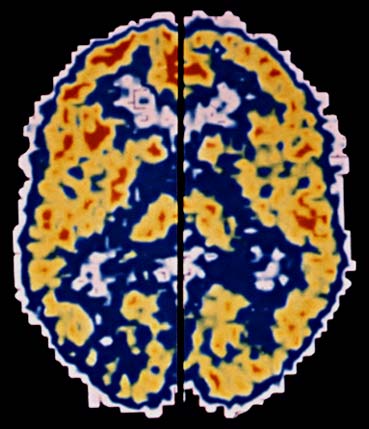

PET che compara l'attivitą del cervello normale (in quest'immagine l'emisfero cerebrale sinistro) con quello sotto l'effetto dell'eroina (emisfero cerebrale destro). La riduzione delle aree rosse e gialle a destra indica il marcato decremento dell'attivitą cerebrale.